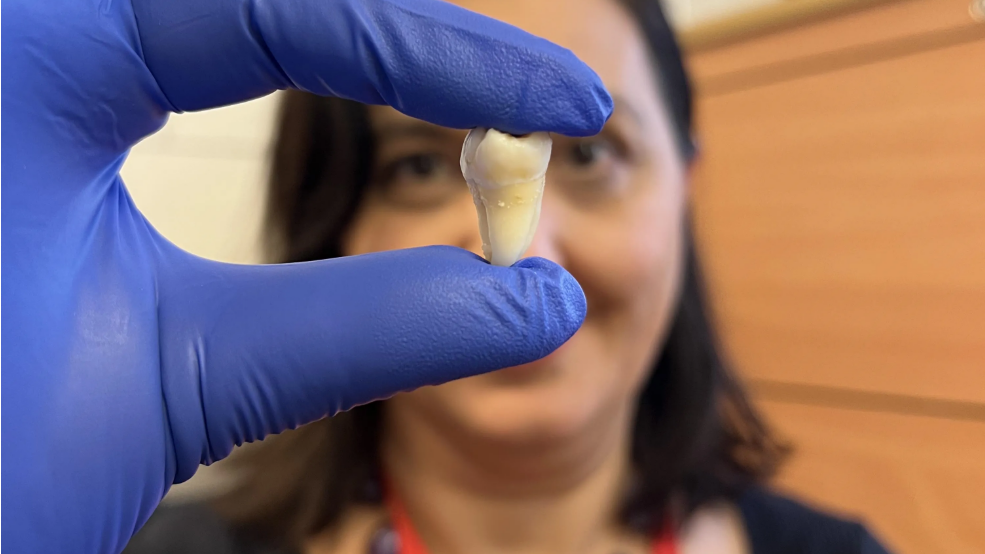

A new U.S. study published Friday in JAMA Health Forum warns that eliminating fluoride from community water systems could lead to increased tooth decay in children and drive up dental costs by an estimated $9.8 billion over five years. “Fluoride replaces weaker ions within tooth enamel, making it stronger and less susceptible to tooth decay … Read more